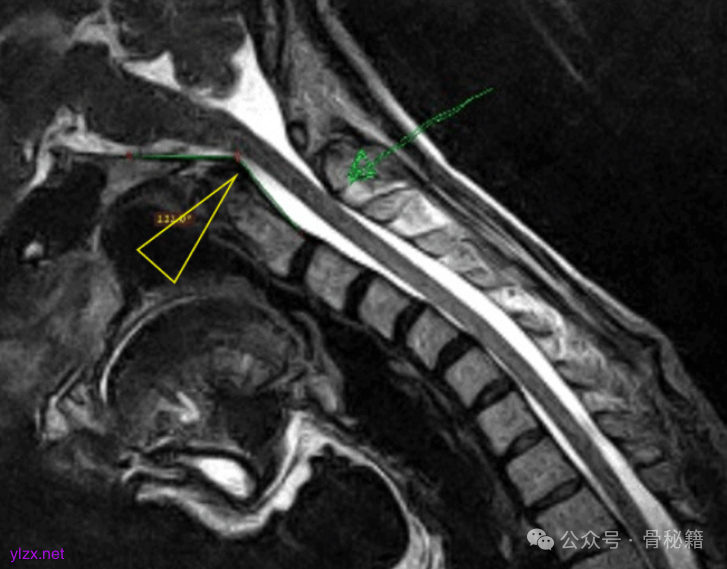

- 颈部 MRI

:可清晰显示颈椎间盘、脊髓及周围软组织病变。

- 磁共振血管造影(MRA)

:用于评估椎动脉及椎基底动脉系统的血流情况。

- 椎动脉造影

:直接观察椎动脉形态及血流动力学变化。

- 旋转椎动脉型眩晕(弓猎人综合征)

:多见于老年患者,头部转动时椎动脉受压,引起椎基底动脉供血不足,诱发眩晕。